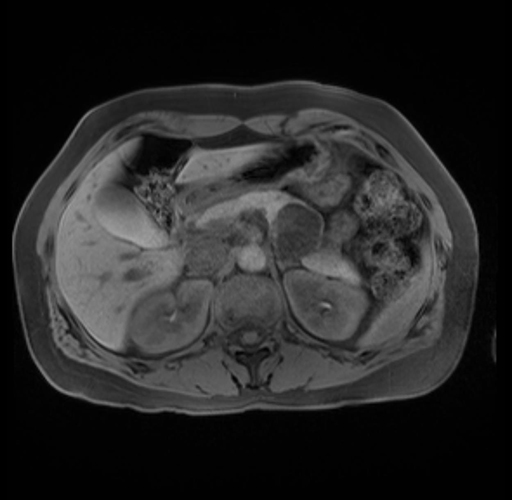

Imaging Analysis

Look through the patient's CT scan to identify any areas of concern for the necessary procedure.

Based on your CT findings, which issue(s) are present and would give reason for "planned slowing down moment(s)" in this case?